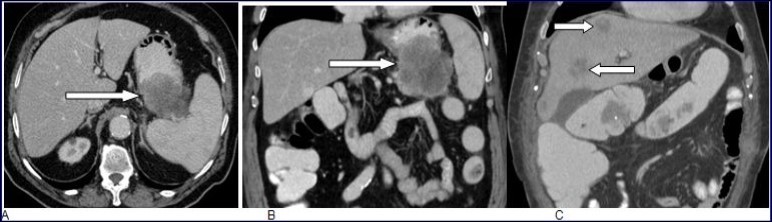

Abdominal CT scan with intravenous contrast material enhancement showed a huge mass of the gastric body, largely necrotic, infiltrating the pancreatic tail, the spleen and the left transverse colon. CT scan did not reveal any other lesion than the except gastric tumor (Figure 1. A, B).

Figure 1.A and B, Abdominal CT scan with intravenous contrast enhancement showed a huge mass of the gastric body, largely necrotic, infiltrating the pancreatic tail, the spleen and the left transverse colon. CT scan did not reveal any other lesion except the gastric tumor. C: Multiples liver metastases two months after surgical operation.

A and B, Abdominal CT scan with intravenous contrast enhancement showed a huge mass of the gastric body, largely necrotic, infiltrating the pancreatic tail, the spleen and the left transverse colon. CT scan did not reveal any other lesion except the gastric tumor. C: Multiples liver metastases two months after surgical operation.

Follow-up thoracic-abdominal CT scan obtained two months after surgical operation showed liver and lung metastasis and multiple retroperitoneal lymph nodes (Figure 1, C). Palliative chemotherapy was then indicated. Unfortunately, the patient's condition deteriorated rapidly and he expired three months later.